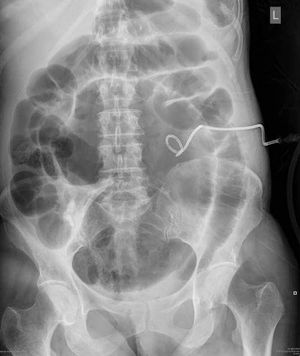

A 59-year-old woman is admitted to hospital after developing an infection of a non-functioning left kidney, Intravenous antibiotics are given and a nephrostomy tube is inserted. During her recovery she starts to develop a distended abdomen and complains of nausea and abdominal pain. An abdominal film is requested: What is the cause of the abdominal distension? A-Bowel perforation B-Intussusception C-Bacterial peritonitis D-Caecal volvulus E-Subcutaneous emphysema